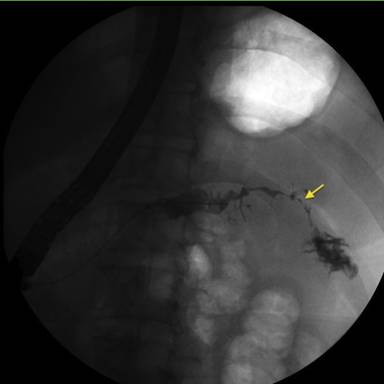

Endoscopic retrograde cholangiopancreatography (ERCP) was performed. The pancreatogram revealed extravasation of contrast from the tail of the pancreas into the colon, confirming the diagnosis of pancreaticocolonic fistula (Figure 1). A pancreatic sphincterotomy was performed and a 10 Fr by 12 cm pancreatic duct stent was placed to the mid pancreatic body to facilitate drainage. Following stent placement, there was purulent drainage from the pancreatic duct. Repeat ERCP 6 weeks later demonstrated persistence of the fistula and re-accumulation of purulent debris within the pancreatic duct. The pancreatic duct stent was replaced, but on follow-up physical examination and ERCP 6 weeks later, the patient had persistent abdominal pain and the fistula had not resolved.

Figure 1. A pancreatogram showing extravasation of contrast from the pancreatic tail and into the colon (arrow), confirming the diagnosis of a pancreatic-colonic fistula. |